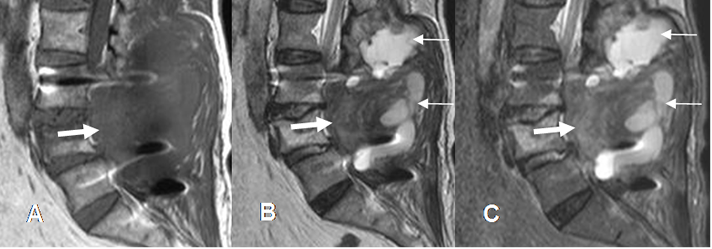

Fig 129B. Compresión postQx.

A: RM sagital en T1, B: RM sagital en T2 y C: RM sagital en STIR. PostxQx de laminectomía y fijación posterior. El paciente evoluciona con paraparesia y se encuentran cambios inflamatorios y colecciones de tejidos blandos. (Flechas delgadas). El canal medular está ocupado por imagen hipointensa en todas las secuencias (Flechas gruesas),

encontrándose un hematoma en la revisión Qx.